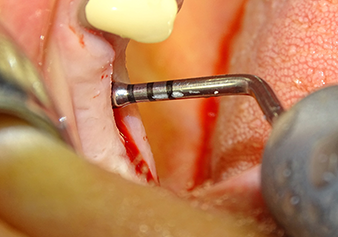

The Schneiderian membrane is stretched 1.5-2 mm above the bony access

Fig.4: Intermediate check: The bone height above the maxillary sinus floor is approx. 4 mm palatal and buccal; the Schneiderian membrane is stretched 1.5-2 mm above the bony access.